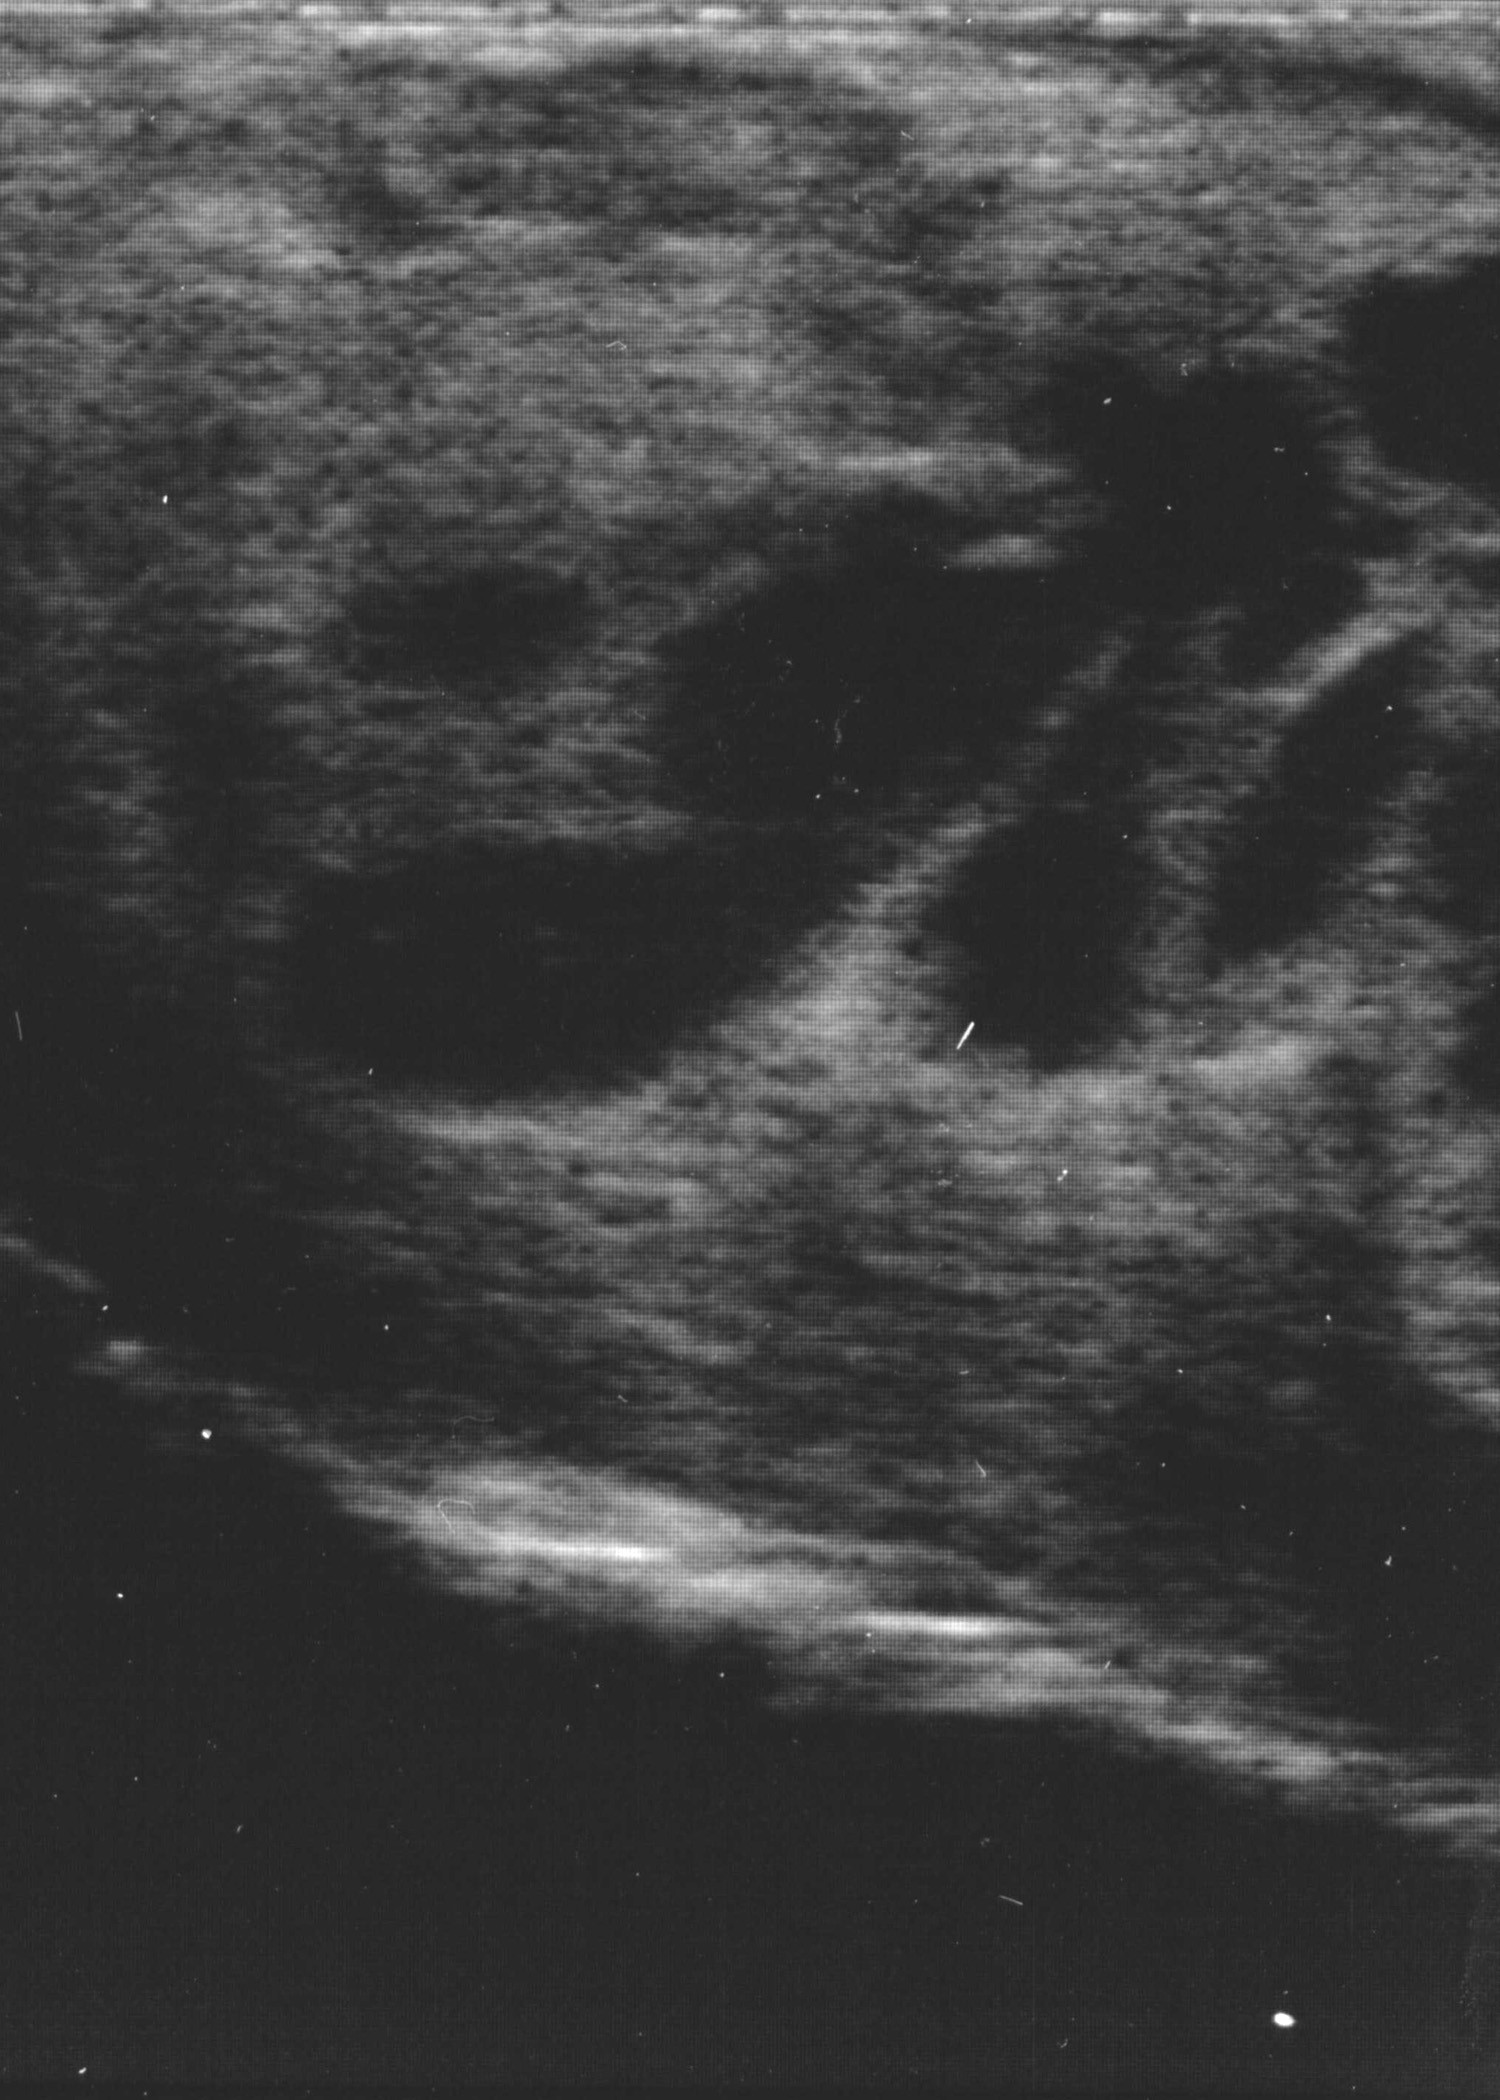

Transrectal ultrasound image of mass:

Aspiration of perirectal mass: Thick, white-yellow purulent material is aspirated.

Cytology of perirectal mass fluid: The fluid contains large numbers of degenerate neutrophils and bacteria, indicating a septic inflammatory process consistent with a perirectal abscess. No lymphoid tissue is seen. Based on the cytology, the fluid is also submitted for bacterial culture.